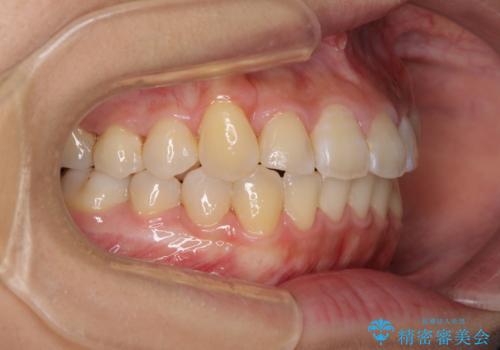

- 前歯のでこぼこと乳歯が残るほどの八重歯を気にして来院された患者様です。

非抜歯にてワイヤー矯正にて治療することとしました。(ただし、親知らずと乳歯は抜歯)

犬歯は歯根が太く長いため、移動には時間を要します。しかし、犬歯は機能面から考えて残すことを選択したいため、長期間をかけて治療を行うこととしました。

治療の度に歯列が改善していったため、長期間の治療も楽しく過ごしていいただき、満足のいく仕上がりとなりました。